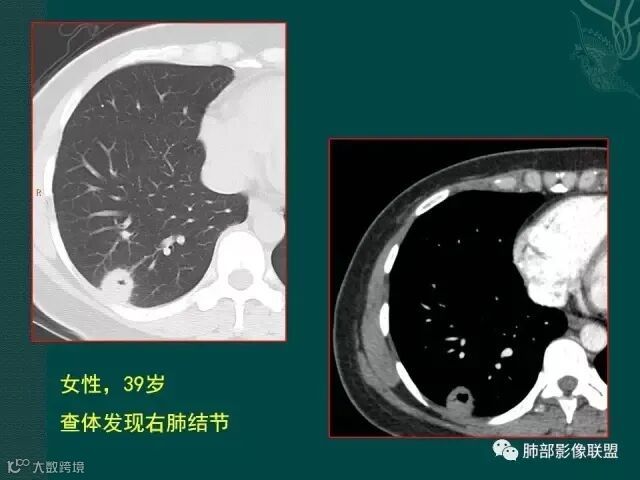

上一个是磨玻璃密度肺癌,边缘清晰,内有分隔,空洞型肺癌伴磨玻璃密度影的,100%为腺癌,很显然这是个假性空洞;

下一个也是肺癌,内有分隔,外下缘箭头所示也是磨玻璃影,这也是腺癌,同时可见叶间裂有转移灶。